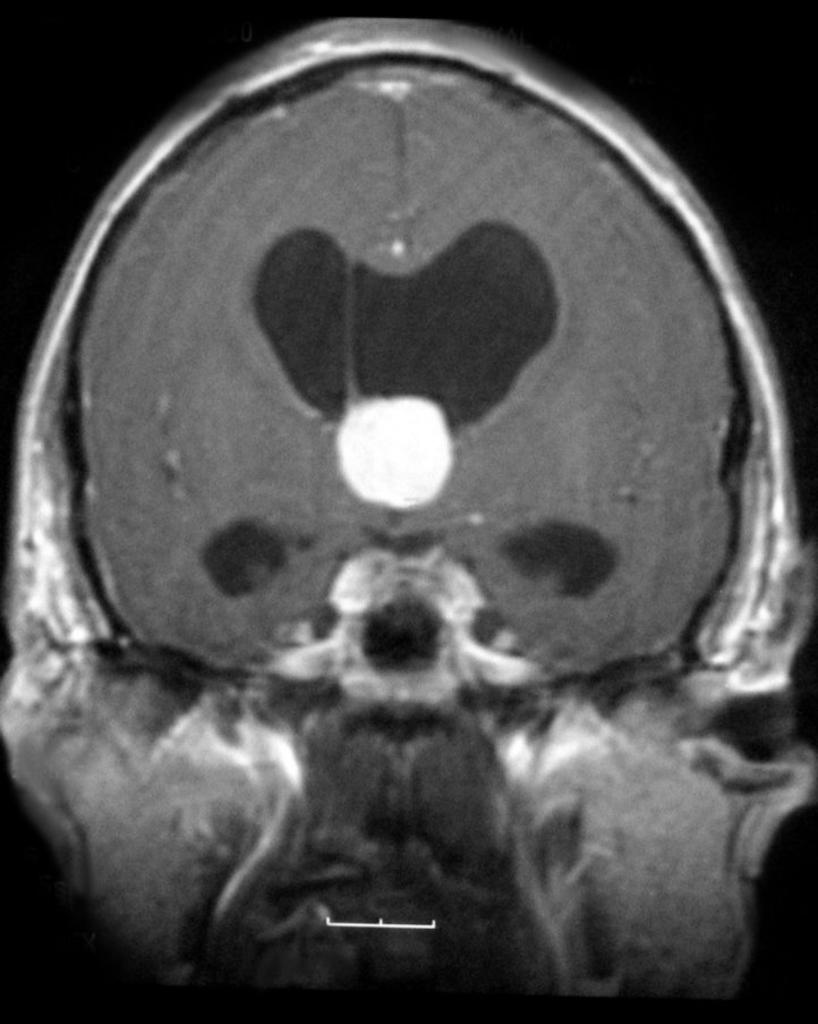

Менингиомы головного мозга на КТ: диагностика и лечение